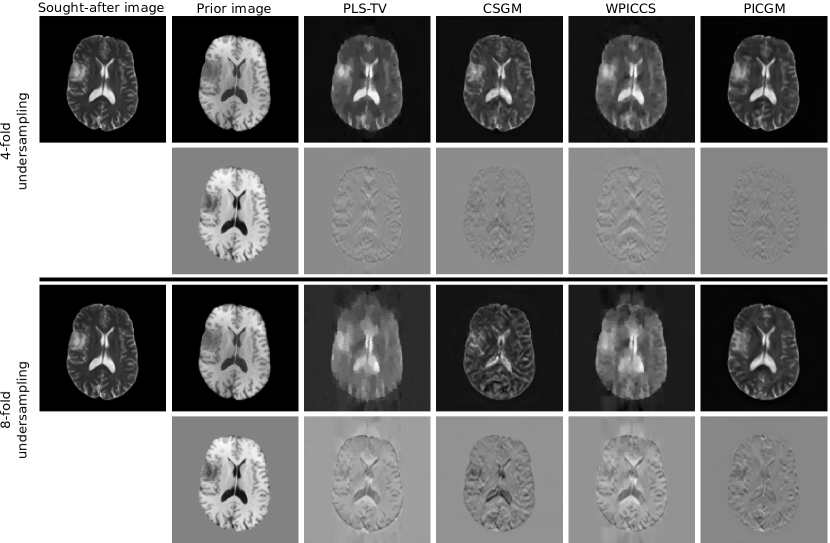

Figure 1: Sought-after image, prior image and image reconstruction results for an axial brain image, for 4-fold and 8-fold Cartesian undersampling and 20 dB SNR. For each undersampling case, the lower row of images shows the difference image with respect to the sought-after image.

Figure 1 shows the images reconstructed using the various methods, from 4 fold and 8 fold simulated undersampled MRI measurements. The root-mean-square error (RMSE) and structural similarity (SSIM) values over a test dataset are shown in Fig. 2. For the case of 8-fold undersampling, although the images recovered by PLS-TV, CSGM and WPICCS all have artefacts, CSGM has noticeably better defined boundaries. The proposed method outperforms all the other approaches examined in terms of RMSE and SSIM. Notably, the hyperparameters p1subscript๐‘1p_{1} and p2subscript๐‘2p_{2} which control the styles that are optimized over remain robust across the test dataset.